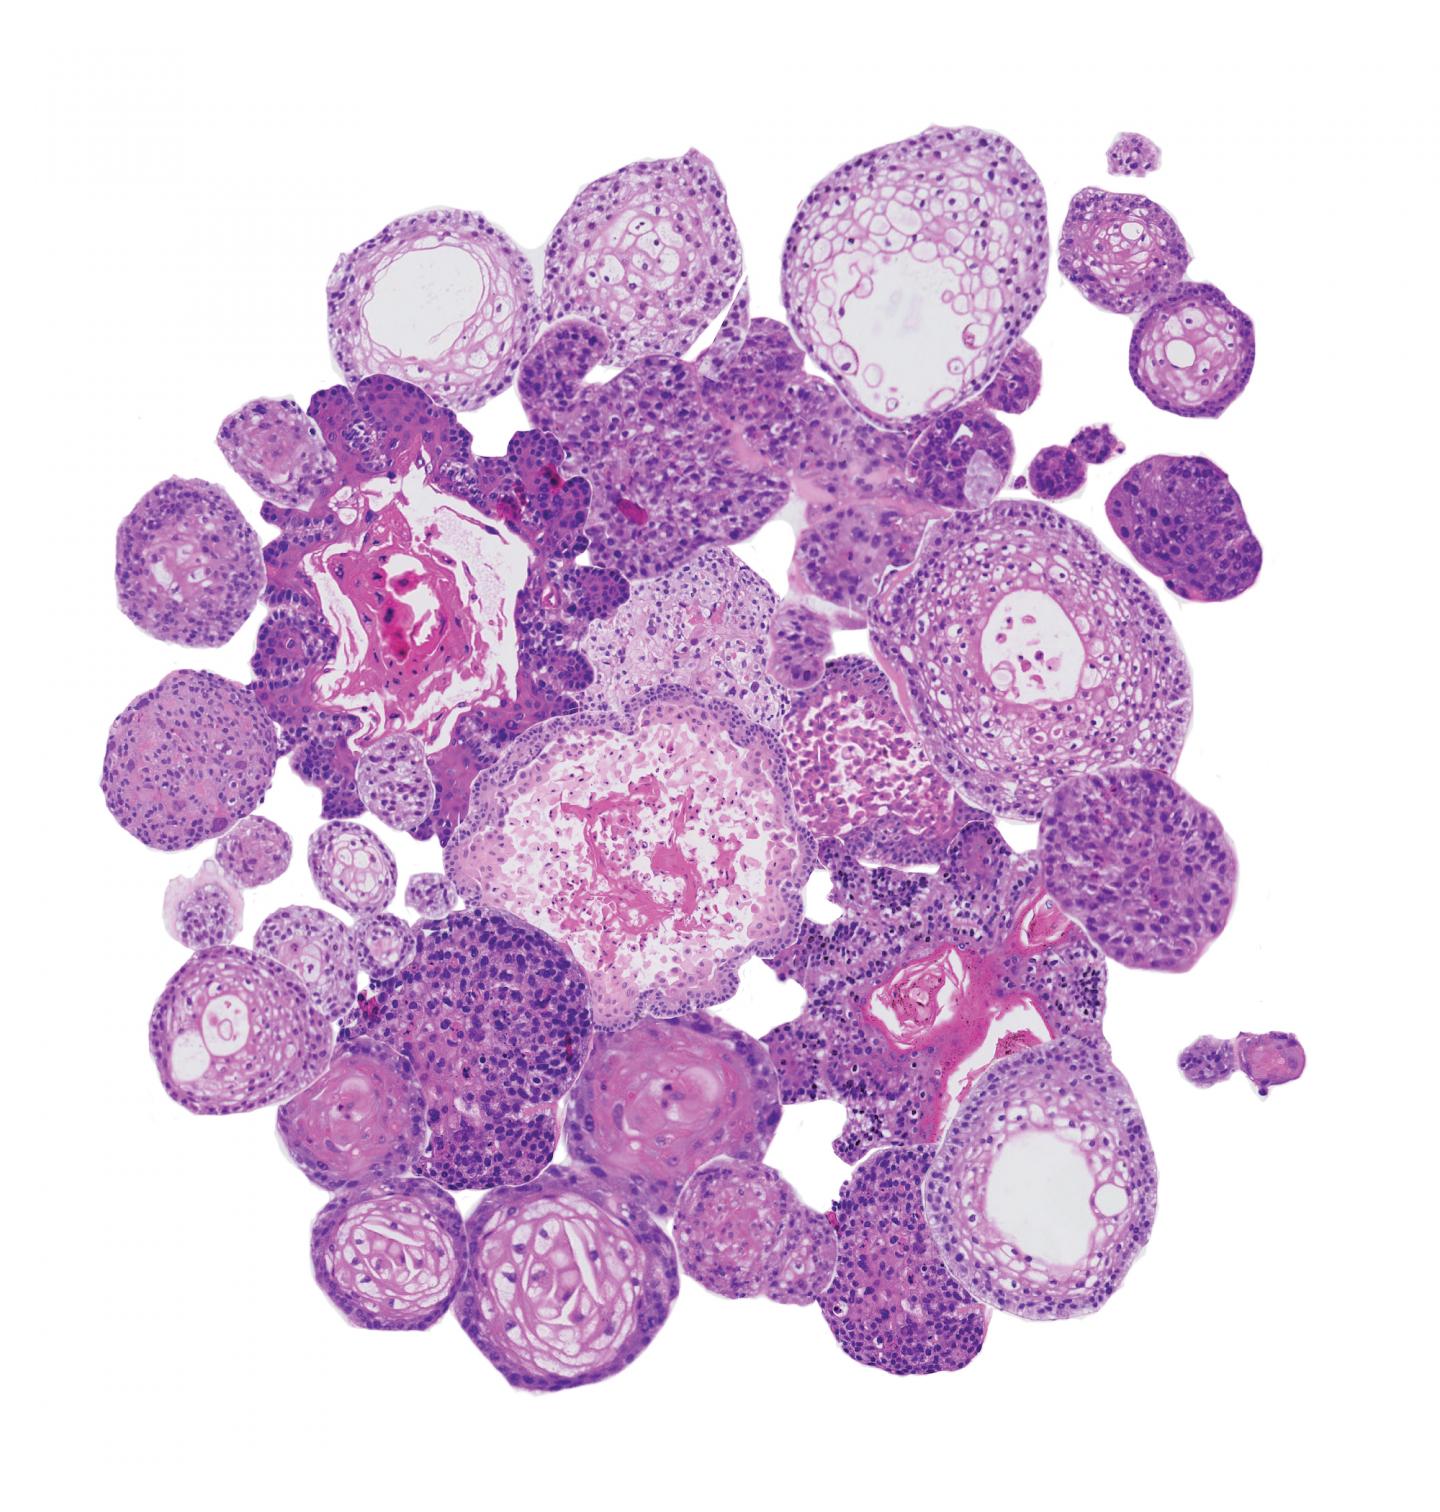

Collage of head and neck cancer organoids, stained with hematoxylin and eosin staining.

Else Driehuis, © Hubrecht Institute